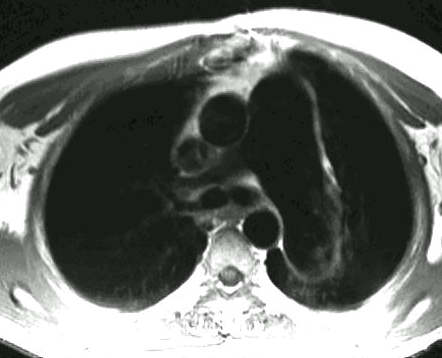

Scott WilliamsMiscellaneous PulmonaryMisc > BonemarrowApril 2, 2002Cardiac ImagingCardiovascular > Thallium > PrognosisApril 2, 2002PETPET > PET tumor imaging > Colon CancerApril 2, 2002Infections-InflammatoryInfect > Granuloma > TB > Images > Case2April 2, 2002TumorTumor > Malignant > TrachealsqcaApril 2, 2002PulmonaryPulmonary > DTPA imagingApril 2, 2002CardiacCardiac > Valve > PS > Images > PS1April 2, 2002PulmonaryPulmonary > V-Q examApril 2, 2002CongenitalCongenital > ImmunoApril 2, 2002TumorTumor > Benign > LipomaApril 2, 2002Previous PagePage 78 of 265Next PageTop StoriesPractice ManagementHPI: Radiology attrition varies by gender, specialty, and practice typeContinuing workforce trends such as increasing subspecialization and practice consolidation could affect the attrition rate.Radiation Oncology/TherapyASTRO: Short prostate SBRT reduces side effects, but not PSA levelsRadiation Oncology/TherapyASTRO: STAR has role in managing VT in cardiac patientsCT5-year CTC screening interval is appropriate for colorectal cancerSponsor ContentDigital Innovations Shaping the Future of Radiology